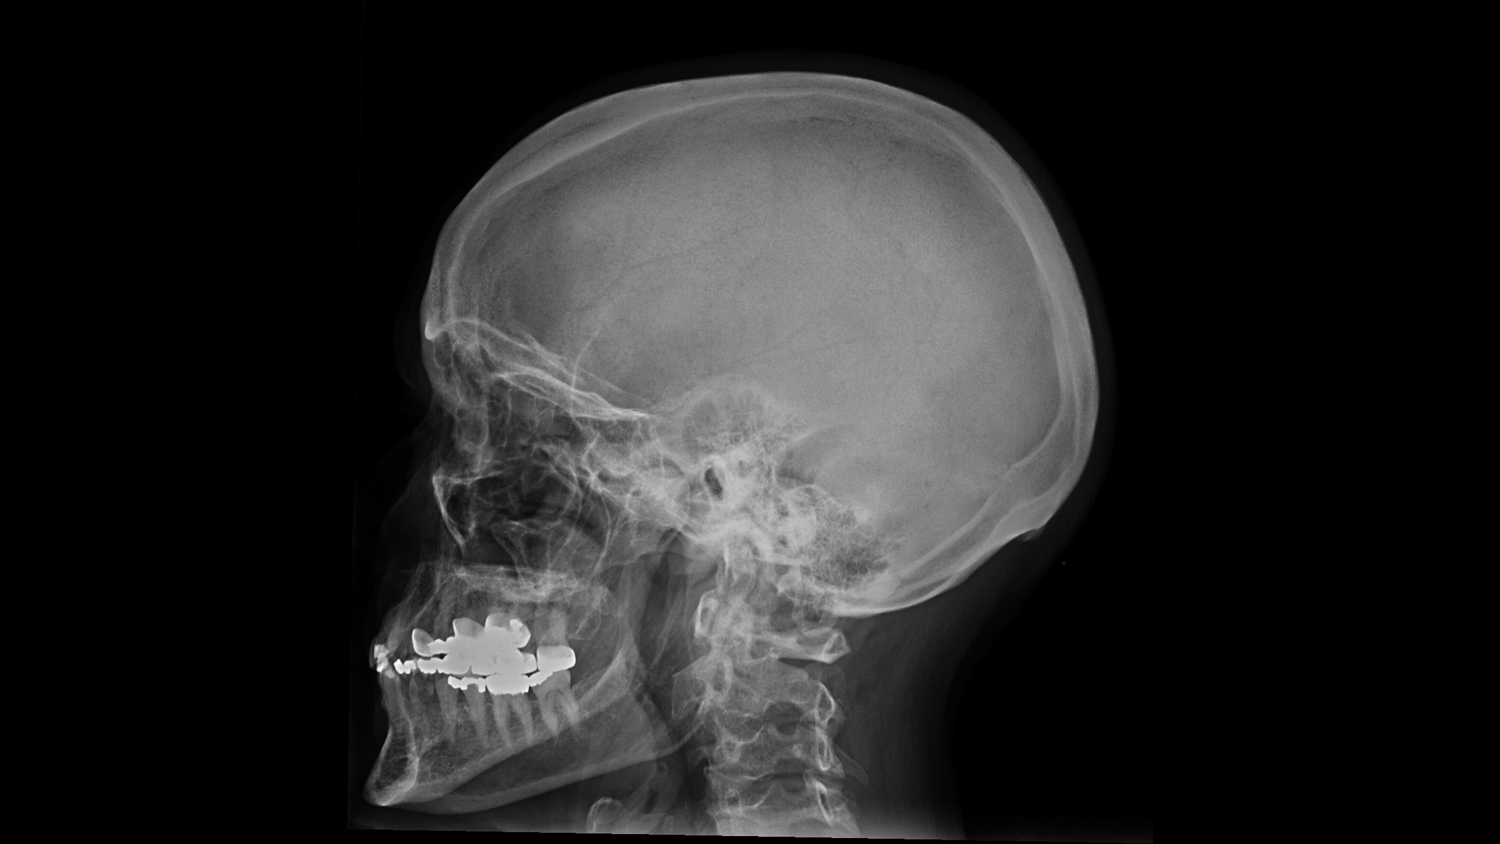

Анатомия мозга: Рентгеновские снимки для презентаций